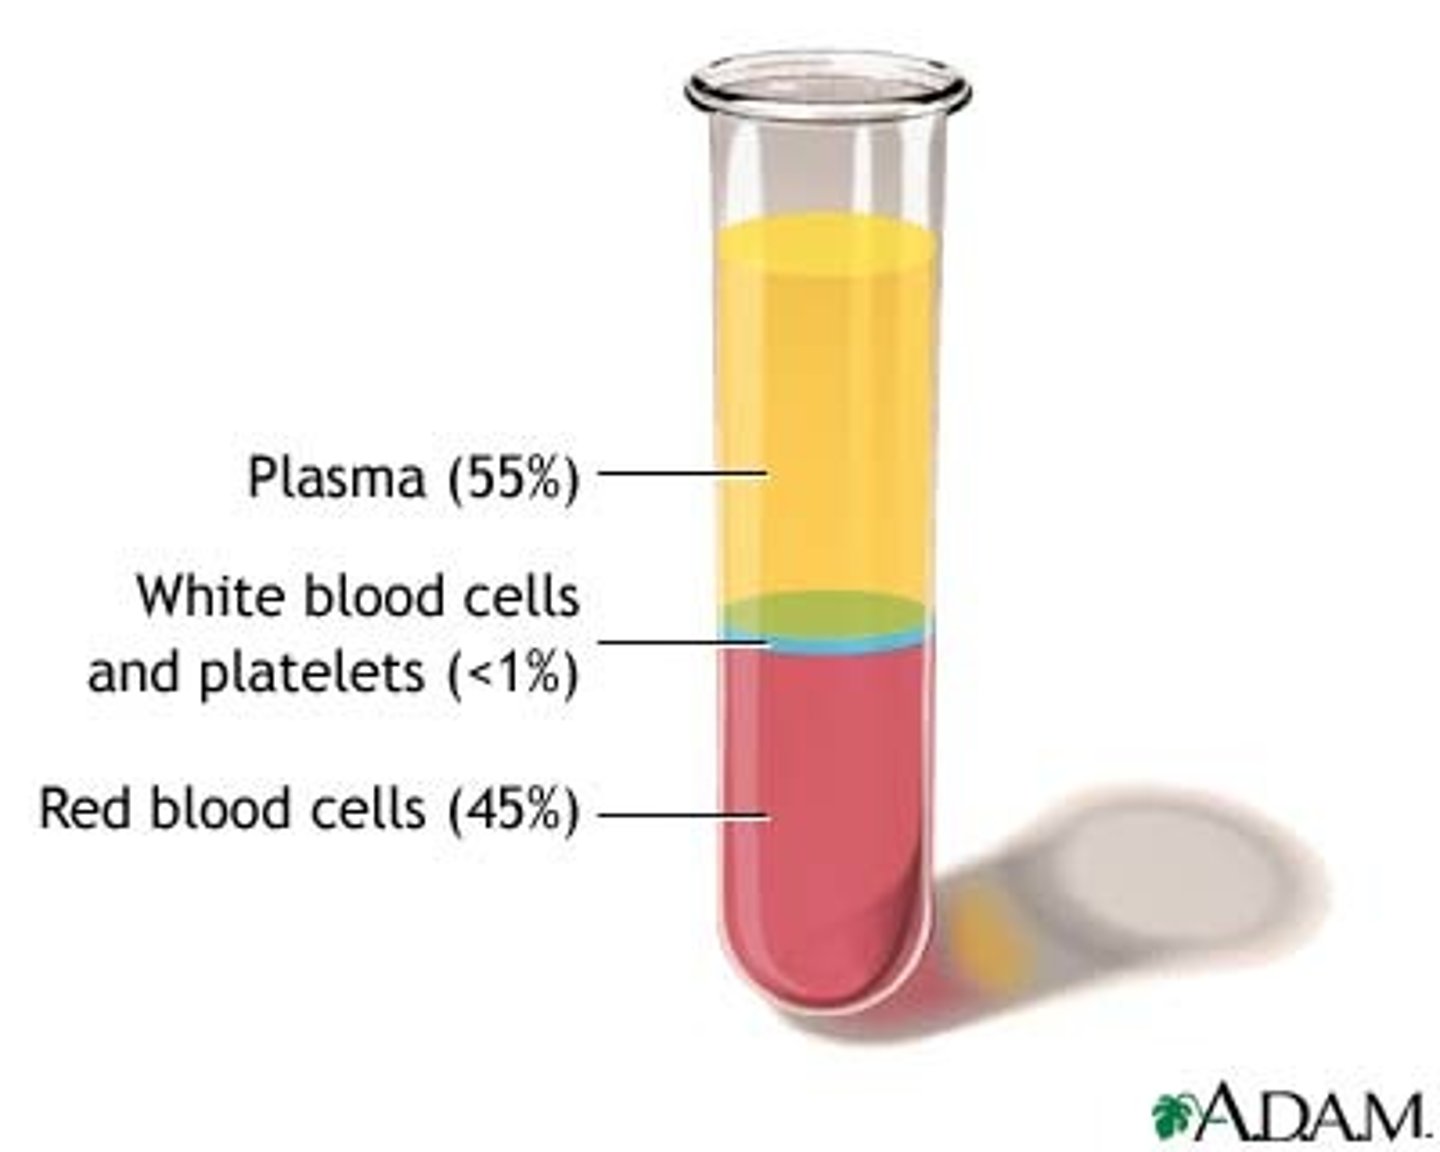

What is the cellular component of blood?

Erythrocytes, leukocytes, thrombocytes (45% of blood)

What is blood plasma?

Liquid part of blood, mostly water and proteins (55% of blood)

Blood fractionation

The process of separating it into its component parts using a centrifuge